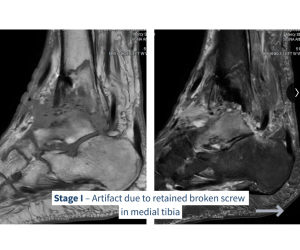

Multistage Limb Salvage for Septic Ankle

Kyle McKray Smith, DPM, FACFAS

#CaseHighlight: Multistage Limb Salvage for Septic Ankle A 70-year-old male presented with a septic ankle and an ulcer tracking to bone after...